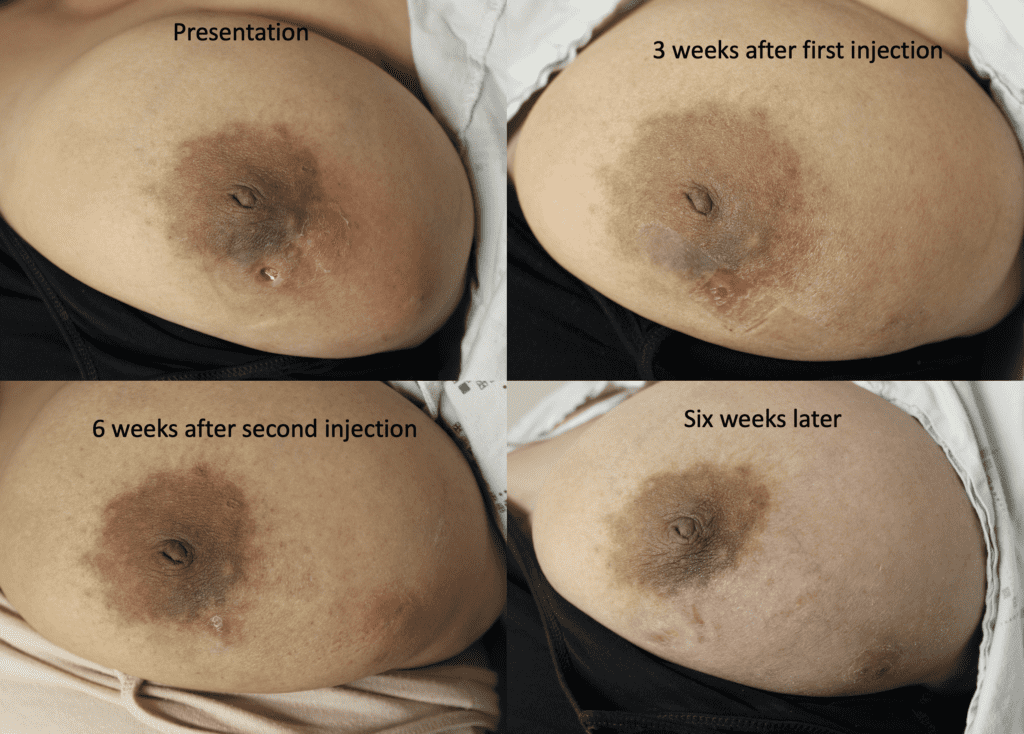

Idiopathic Granulomatous Mastitis (IGM or GM)

Idiopathic granulomatous mastitis (IGM) is an inflammatory disorder affecting the breast of young women in their childbearing years, and can overlap with lactation and pregnancy. It can result in development of painful inflammatory masses, fluid collections, and fistula formation. While breastfeeding from the affected breast in the setting of IGM is safe, many mothers report significant pain and difficulty with latch or milk production.

The definitive treatment for IGM is immunosuppression with the oral medications methotrexate (not safe with lactation or pregnancy) or azathioprine (safe with pregnancy and lactation). This case report describes continued breastfeeding and resolution of IGM with azathioprine therapy.

I have had similarly impressive results in my IGM patient population. I first prescribed LDN in the summer of 2024, and the patient resolved completely by the fall. Many others have resolved within just a month or two. All have experienced improvement within a month. Only one of my patients has remained symptomatic, but her disease is far better and far less painful than before (consistent with the Crohn’s Disease literature). Some of these patients are pictured below – keep scrolling :).

Another option for treating a flare of IGM is a steroid injection into the affected breast. This video that I presented at the American Society of Breast Surgeons in Boston spring 2023 illustrates this procedure:

While some cases of IGM may resolve from a simple mass, many go on to form fluid collections (above and below) that may drain on their own. These are mistakingly called “abscesses.” They are in fact just fluid collections of dead inflammatory cells. Patients need either local treatment with needle drainage of the fluid (NOT large incisions with packing tape, which make inflammation worse) and steroid injection, or oral steroids/anti-inflammatories/immune suppressants.